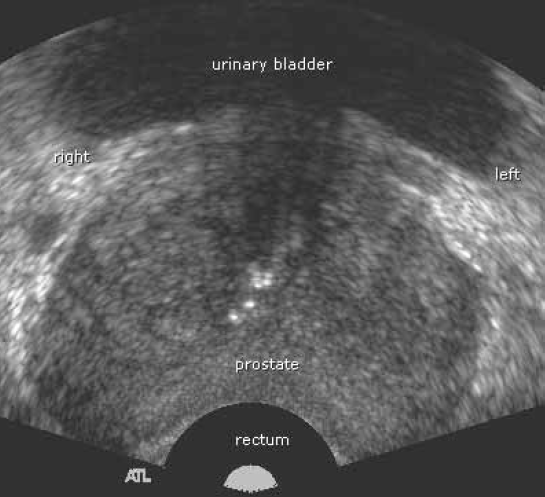

what plane is this?

saggital

trans